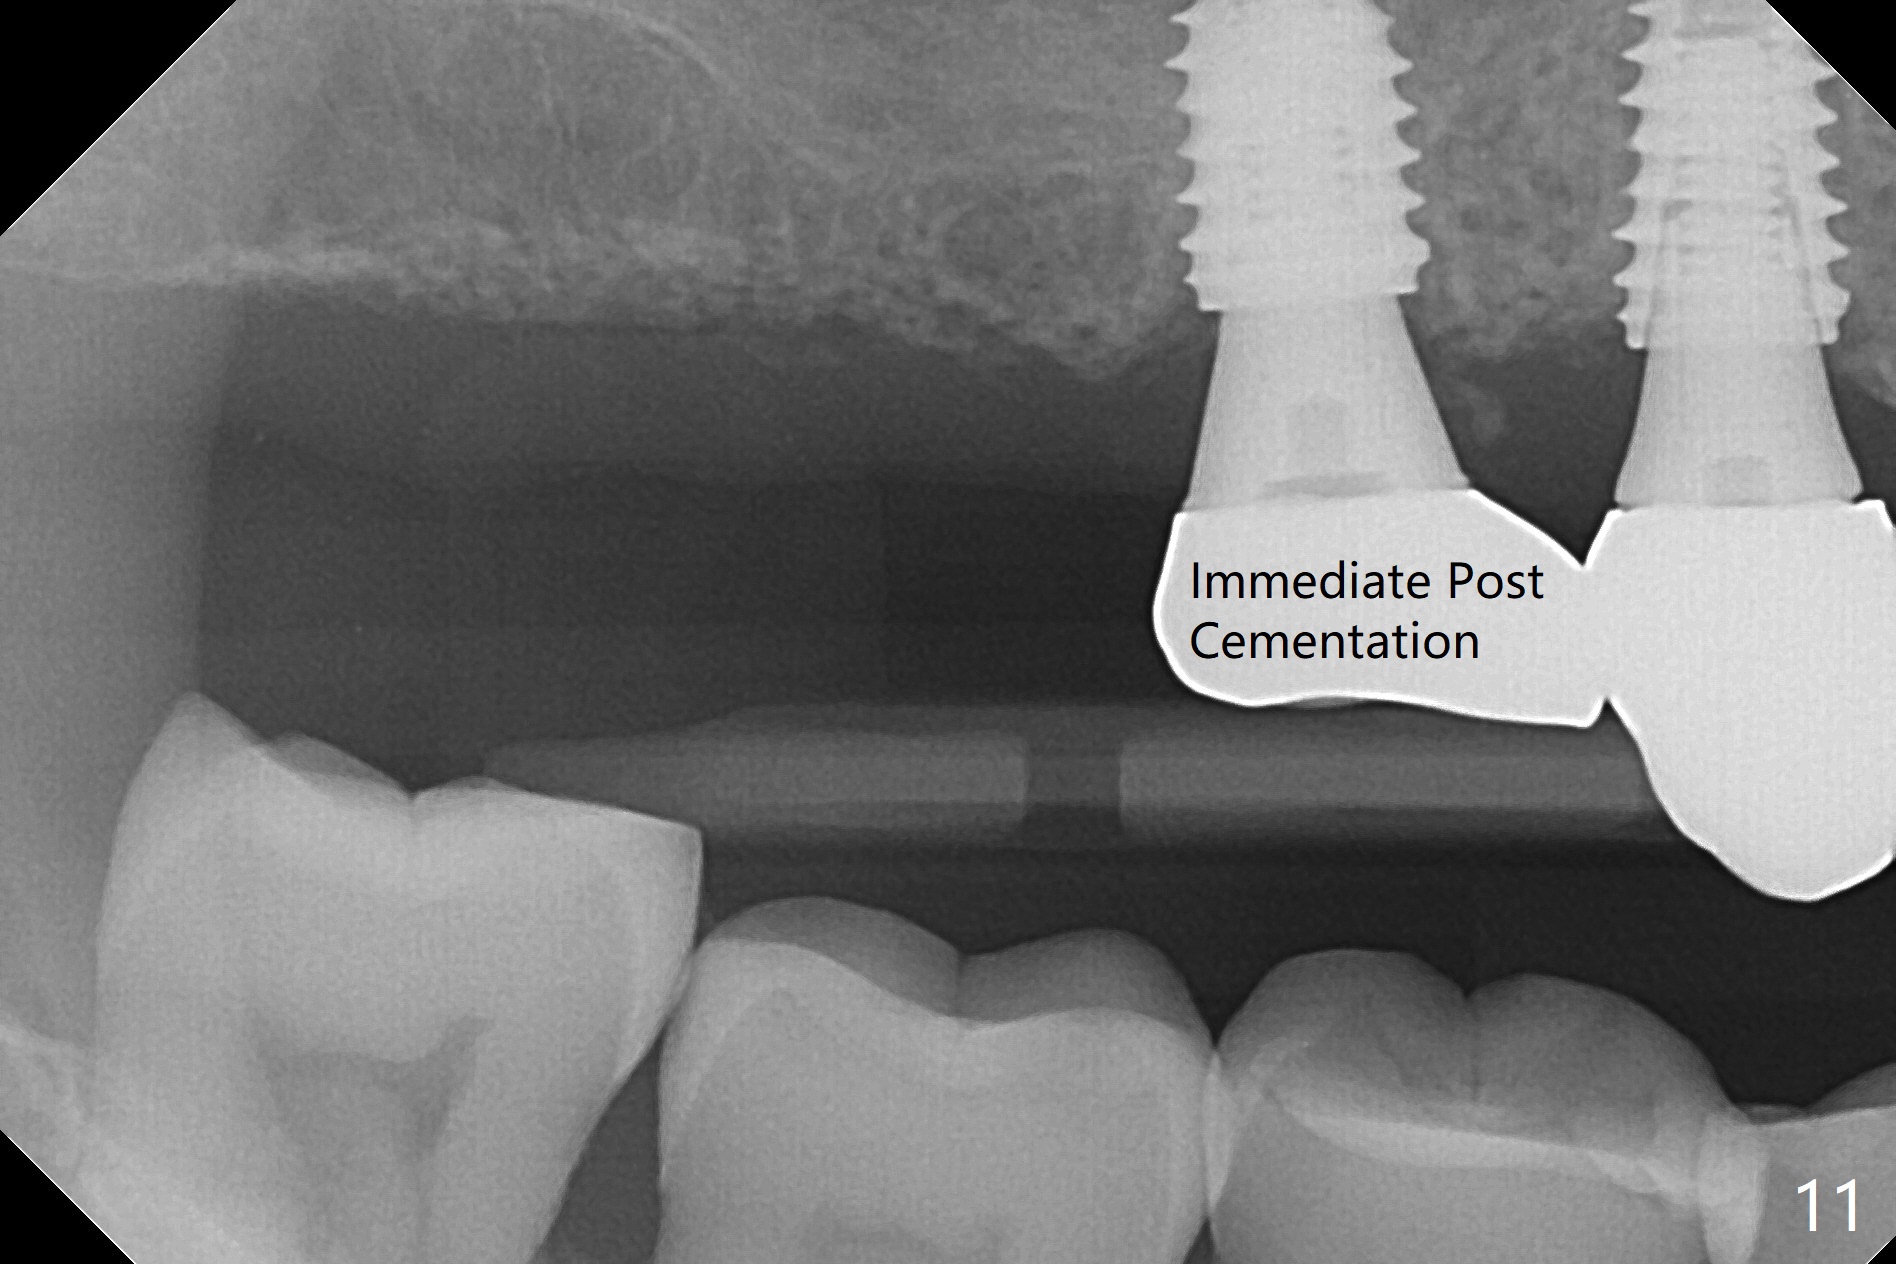

Osteotomy at #3 is performed last (Fig.1,2); as planned, a 4 mm cortical tap is used with guide for sinus lift. Unfortunately the sinus membrane is perforated. Implant placement is aborted. Instead Osteogen plug is inserted into the osteotomy, which is fixed in place by acrylic extending from the provisional at #4. Osteotomy for #3 implant will be attempted with control of the depth in 4 months. The patient has allergy to Amoxicillin (rash). When switching to Clindamycin, she develops diarrhea and loses 10 pounds. There is no abnormality at the site of #3 or 4 nearly 3 months postop (Fig.3). The next surgery will be most likely conducted without antibiotic 4 months postop. Try to draw blood for PRF. Take PA for #12 and 13 for possible impression. Remove the 3 temporary crowns, seat the guide across the arch and use no-stop fixture mounts at #4, and possibly 12 and 13. Follow the original drill sequence (check perforation after each drill, Fig.11) and use DIONavi sinus approach kit. Also load an appropriate stop for the round bur for sinus lift before hand. Mixture allograft with Metronidazole and PRF. In fact everything goes on as smoothly as planned. Osteotomy at #3 is underprep (3.5 mm in diameter drill instead of 4.0). The sinus floor appears to remain to be absent; 3.2 mm round bur is used for lift, alternating with water pumping. Following insertion of 3 pieces of PRF membranes and Vanilla Graft (Fig.4 *), a 4x10 mm dummy implant is placed. After additional bone graft (Fig.5 *), a final 4.5x7.3 mm implant is placed ~10 Ncm. The implant is placed deeper ~ 1 mm, followed by a 5.5x3 mm healing abutment (Fig.6). The implants at #12 and 13 seem to have osteointegrated (Fig.7). Impression is taken for #4, 12 and 13 with limited vertical space (Fig.8,9). An implant at #14 is being considered. There is faint bone graft around the apex of the implant 4 months postop (Fig.10). The implant sustains 25-30 Ncm torque when a 5.2x4(3) mm cemented abutment is placed. A permanent crown is cemented nearly 5 months postop (Fig.11). For the best cosmetic and masticating results, the occlusal surface should have certain degree of morphology, such as the buccal cusps (Fig.12 white curved lines). The abutment at #3 is placed and torqued to 30 Ncm before re-cementation of the repaired crown (increased occlusal surface contact). In fact the abutment at #4 is incompletely seated with a gap (Fig.13 <). The composite at #5 is dislodged while #3 crown is being repaired (*). The abutment at #4 is loose >1 year post cementation. The abutment remains incompletely seated (gap and longer apical space (double arrows)) when the abutment/crown complex rotates lingual mesiobuccal (Fig.14 curved arrow). Further proximal reduction and lingual rotation distobuccal leads to complete seating (Fig.15). It appears that incomplete seating at #13 is associated with hex mismatch (Fig.16, large apical space), which will be fixed next visit. One week later, the crown and abutment of #4 are seated together after crown repair (Fig.17). Since the abutment margin is subgingival, the crown is cemented, removed with abutment for residual cement removal and reseated with the abutment with torque at 30 Ncm. After this, the crown and abutment of #13 is reseated after mesiobuccal surface is trimmed (Fig.18), followed by pick up impression. A few days later, the crown/abutment are inserted together smoothly, the former cemented and the complex unscrewed for residual cement removal and last torqued at 30 Ncm without any X-ray confirmation.